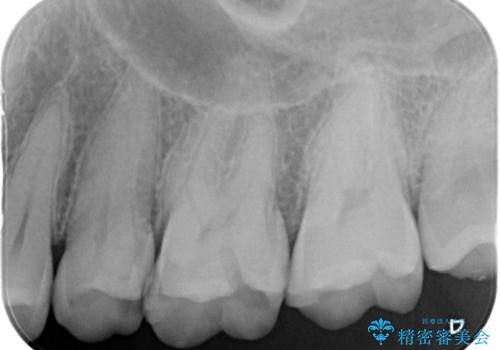

- 歯と歯の間で見つかりづらい虫歯でしたが、顕微鏡で確認し患者様に説明することで理解していただき、セラミックインレーにて修復治療を行いました。

以前にプラスチックの材料で修復した箇所が虫歯として見つかることはよくあります。

- 14万円費用は治療当時の料金となります